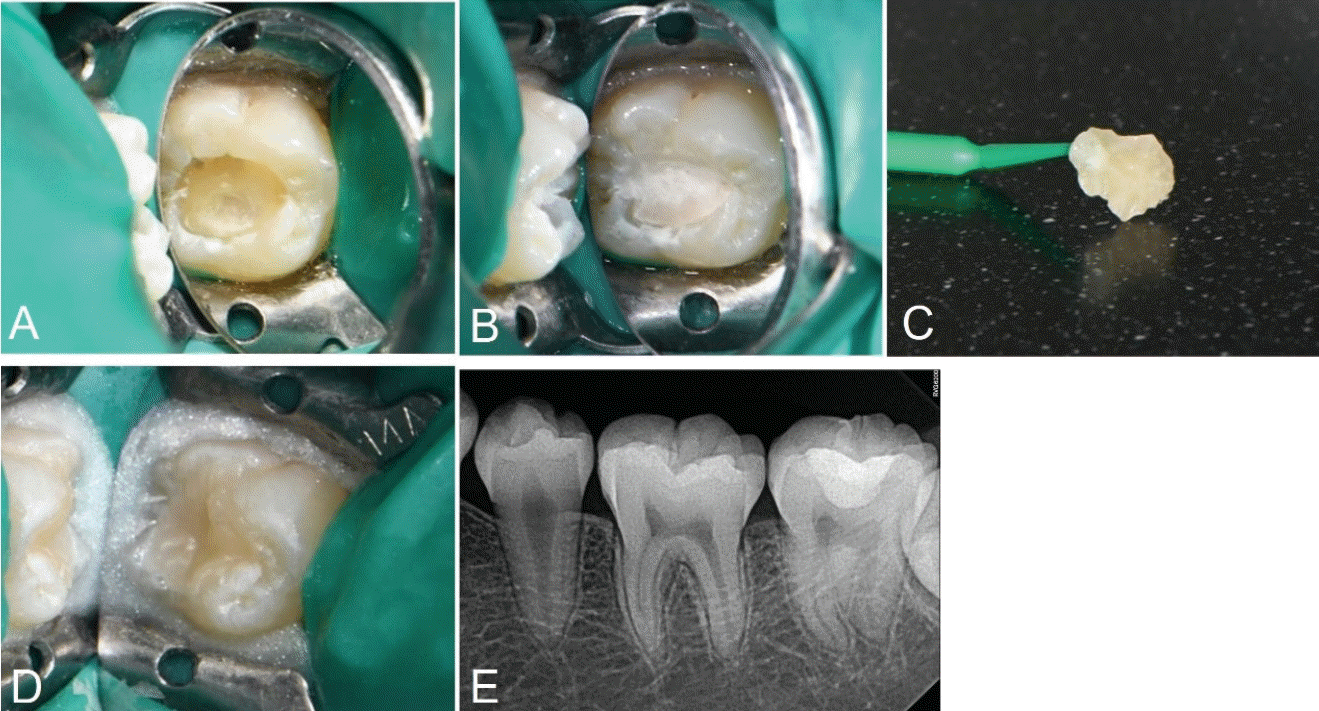

Fig. 2.

A. Caries excavation and cavity preparation is done. B. Base restoration with glass ionomer is done. C. Stamp is obtained using flowable resin and microbrush. D. Photograph after applying stamp on teeth. E. Postoperative periapical radiograph